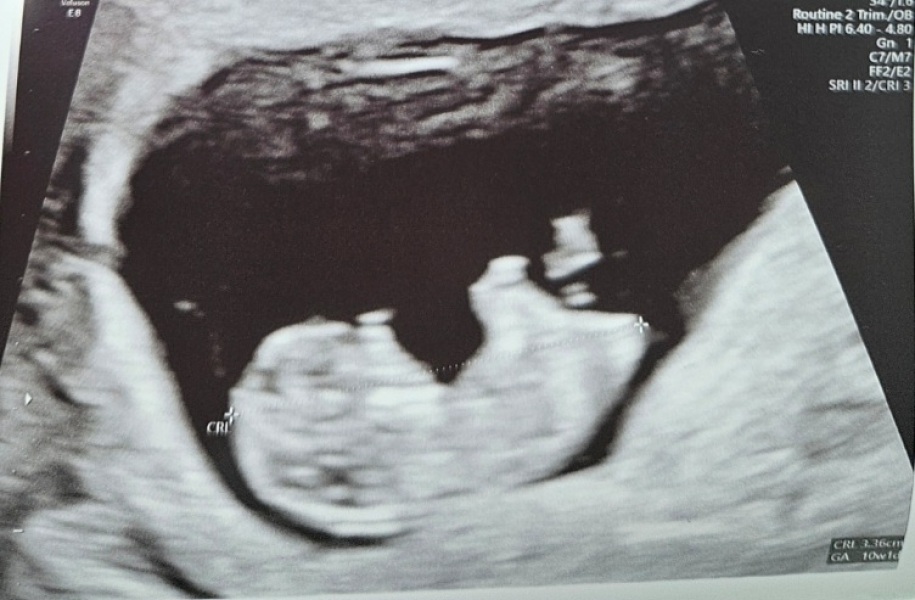

SureLook · 01/10/2025 06:30

We have a live and kicking baby with a healthy heartbeat! Measuring exactly at 10+1. The relief ❤️

I meant to send this yesterday but I was so exhausted with relief 😭😂